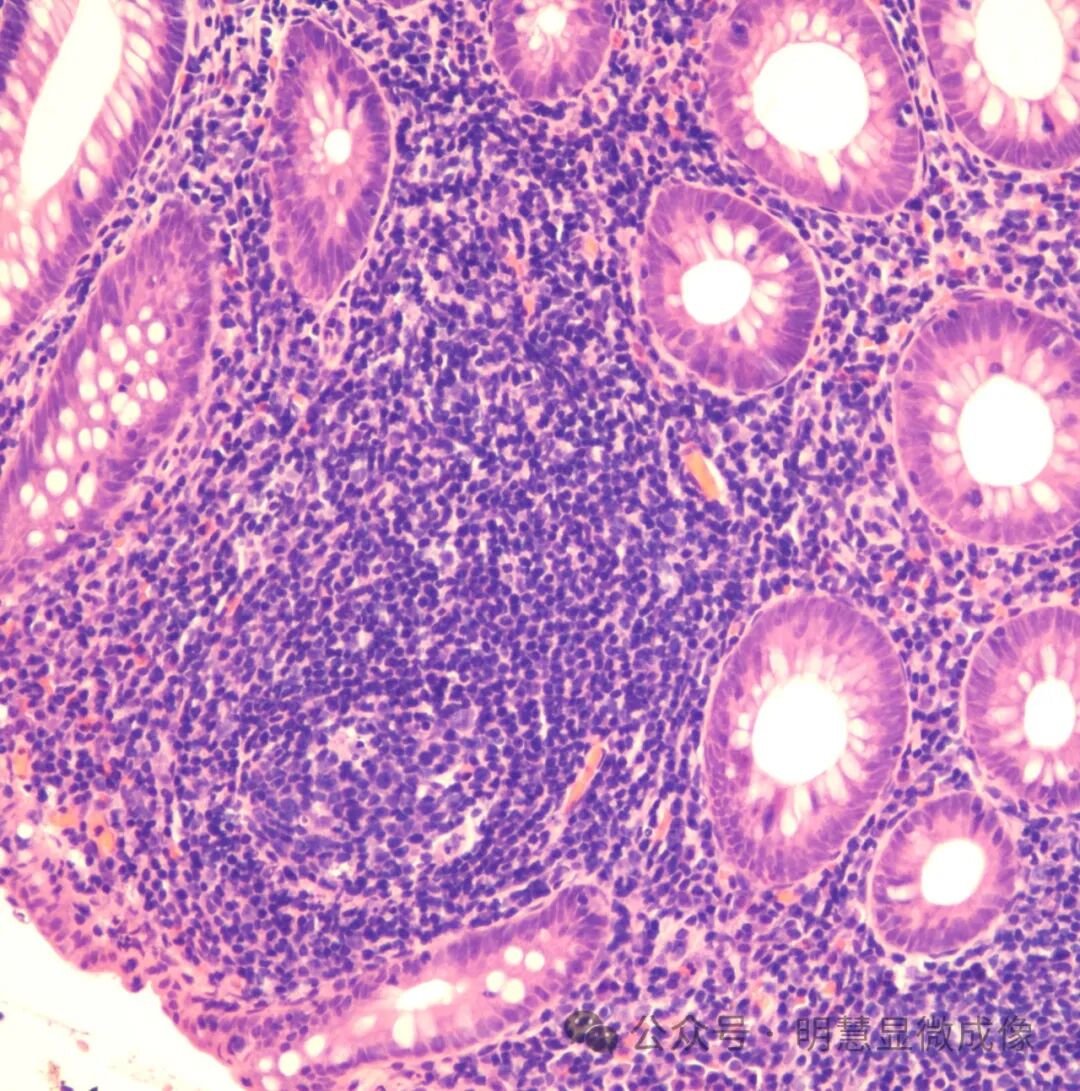

惭贬顿2000实拍效果图